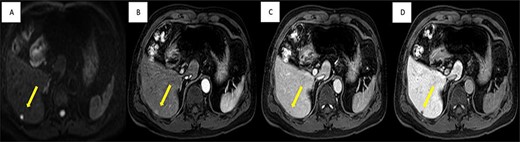

A liver lesion was observed incidentally on the ultrasonography of the kidney-urinary bladder system indicated for benign prostatic hyperplasia in a 69-year-old man. Hepatocyte-specific contrast (gadoxetate disodium) magnetic resonance imaging (MRI) revealed a round 6-mm lesion that was hypointense on T1-weighted images, slightly hyperintense on T2-weighted images and highly intense on diffusion-weighted images. In the contrast-enhanced phase, the lesion showed arterial hyperintensity and hypointensity in the venous and delay phases. Furthermore, a defect in the hepatocyte-specific contrast phase was observed in liver segment 6 (Fig. 1). On laboratory examination, his complete blood count revealed a white blood cell count of 6200/mm3 (lymphocytes, 23%; neutrophils, 62%), haemoglobin level of 16 g/dl and platelet count of 215 × 103/mm3; his liver function tests revealed a total protein level of 7.8 g/dl, albumin level of 4.1 g/dl, a total bilirubin level of 0.68 mg/dl, serum aspartate aminotransferase level of 26 IU/l, serum alanine aminotransferase level of 29 IU/l and alkaline phosphatase level of 105 IU/l. The levels of tumour markers, including alpha-fetoprotein, carcinoembryonic antigen and carbohydrate antigen 19-9, were all within normal limits. Viral markers for hepatitis B and C were negative. Given the classical pattern of contrast enhancement of the tumour on MRI, no history of liver cirrhosis and normal levels of tumour markers, we first considered performing a tumour biopsy. However, we judged that it would be insufficient to make a definite diagnosis. Therefore, we concluded on a diagnosis of HCC and performed laparoscopic partial hepatectomy using indocyanine green (ICG) fluorescence. Intraoperatively, the gross tumour pathology revealed a 7-mm greyish-white solid nodule, and positive staining with ICG was observed (Fig. 2). The gross tumour pathology revealed a 7-mm greyish-white solid homogeneous nodule. The microscopic of nodule showed lymphoid cells proliferation and lymphoid follicles formation with germinal centre (Fig. 3A). Immunohistochemical results were as follows: CD3+ T cells (Fig. 3B), CD20+ B cells (Fig. 3C), BcL-2+ non germinal centre (Fig. 3D), Ki-67 (increased proliferation in germinal centres) and no restriction. The diagnosis of RLH was finally confirmed. His post-operative course was uneventful, and he was discharged on post-operative day 3.

Imaging findings; MRI shows well-defined 6-mm nodule (yellow arrow), (A) strongly high signal intensity in diffusion-weight image, (C) slightly enhanced in arterial phase, (C) low signal intensity in portal phase and (D) non-uptake in hepatobiliary phase.